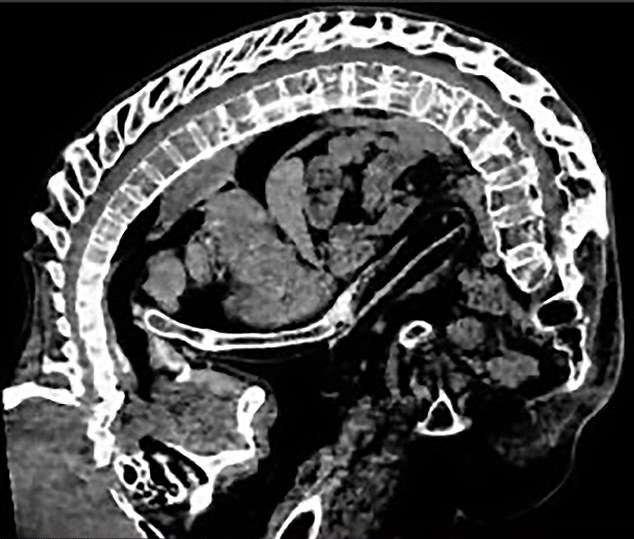

그는 사진과 함께 공개된 정보을 보고 선전대 종합병원의 척추골병과 주임 타오후이런 교수에게 연락했다. 그러자 타오 교수는 리 씨의 사연을 듣고 병원으로 오라고 말했다. 그리하여 리 씨는 노모와 함께 해당 병원을 찾아갔고, 타오 교수는 놀라지 않을 수 없었다. 지금까지 여러 환자를 수술해온 그 역시 리 씨처럼 심각한 상태를 본 적이 없었기 때문이다. 게다가 정밀 검사 결과는 더욱더 심각했다. 리 씨의 아래 턱은 흉골, 가슴뼈는 치골, 얼굴은 주골에 밀착돼 있었는 데 이를 본 타오 교수는 3개소가 접힌 사람이라고 묘사했다.

이에 대해 타오 교수는 “리 씨의 위험은 일반 환자의 20~30배였으며 하반신이 마비될 확률도 높았다. 그렇지만 이대로 그의 수술을 포기해 심장과 폐에 걸린 압력을 낮추지 못하면 생명에 큰 위협이 될 수도 있었다”면서 “다른 환자들은 여전히 머리를 들 수 있었지만, 그는 그럴 수조차도 없는 상황이었다”고 설명했다.